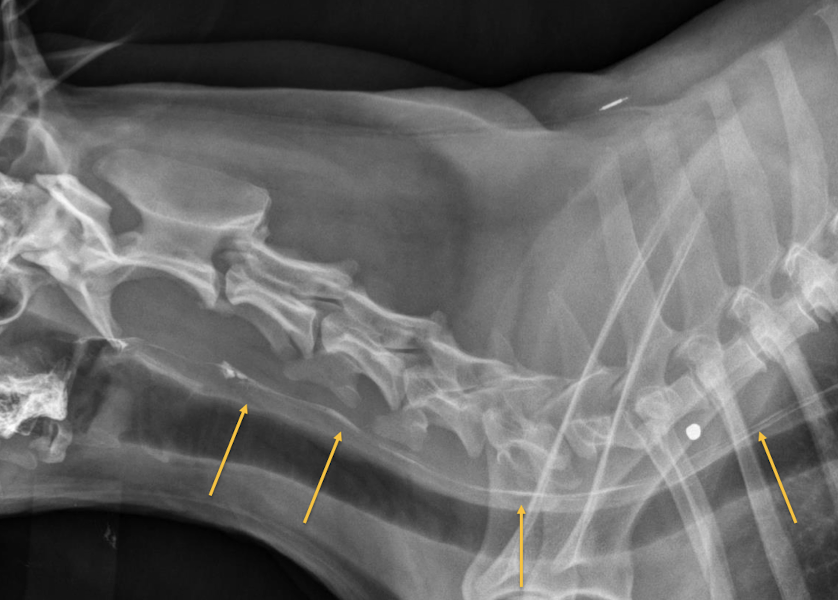

A

Persistent right aortic arch

What is a key finding for persistent right aortic arch?

Focal leftward deviation of the trachea